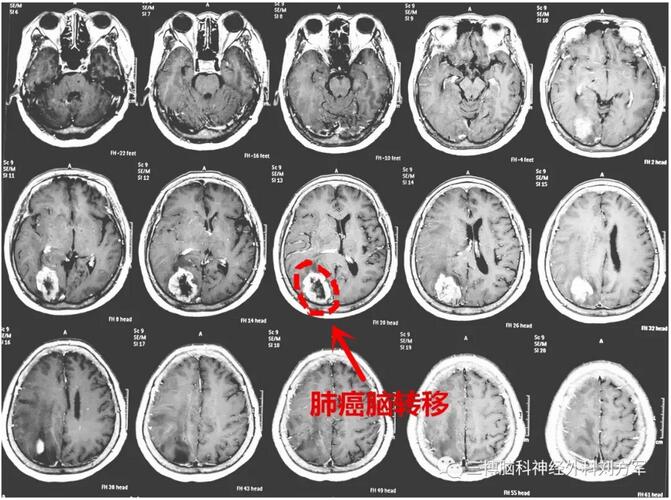

女性,68岁,头痛,视力下降,左侧肢体活动不灵活。诊断:右侧枕叶转移瘤,原发病灶为肺癌。右侧顶枕开颅肿瘤切除术。术后恢复好。病理:转移瘤。出院行放疗及化疗。ps:大的感触就是,治疗过程中,一家人面对困难,积极乐观的承担。老太太特别讲究,出院后,回当地之前,一定要到办公室和我们合影,道别!